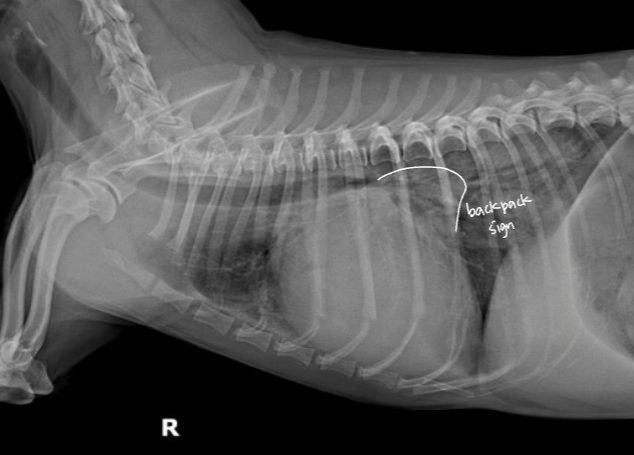

| 1) LCHF |

| Radiographic signs - Pulmonary edema - PV enlargement - (cats) pleural effusion, patch alveolar pattern - LA enlargement (backpack sign, double wall sign) - alveolar pattern |

![]() ![]() |